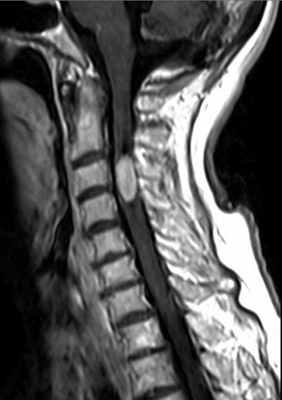

Невриномы (шванномы) и нейрофибромы составляют примерно половину опухолей этой локализации и 35% от всех спинальных опухолей. Гистологически невриномы происходят из шванновских клеток оболочек нерва (леммоцитов), прилегающих к заднему корешку. Обычно диагностируются они в возрасте 20 – 50 лет, у мужчин проявляются несколько в более молодом возрасте, чем у женщин. Они почти всегда одиночные, инкапсулированные, располагаются в любом отделе, но чуть чаще в поясничном или верхнем шейном. Множественные невриномы встречаются исключительно редко при нейрофиброматозе типа II. Нейрофибромы состоят из шванновских клеток и фибробластов, некоторые окружают задний корешок. Они почти всегда множественные и связаны с нейрофиброматозом типа I (болезнь Реклингхаузена). От 2 до 12% нейрофибром перерождаются злокачественно, превращаясь в нейрофибросаркомы. Несмотря на различие в гистологии характер роста опухолей одинаковый. Около 15% из них распространяются в экстрадуральное пространство через одно или несколько межпозвоночных отверстий, приобретая вид “песочных часов”. Такой тип роста особенно типичен для шейной локализации. На рентгенограммах рост по типу «песочных часов» может быть выявлен по расширению межпозвоночного ответстия и эрозии корня дуги. Клинические проявления неврином и нейрофибром состоят в радикулопатическом и миелопатическом синдромах.

На МРТ Т1-взвешенного типа и невриномы, и нейрофибромы изо- или слегка гипоинтенсивны по отношению к спинному мозгу. Однако, встречаются случаи и повышенного сигнала за счет сокращения Т1 мукополисахаридами, связанными с водой. Протонная плотность при МРТ повышена, а на Т2-взвешенных МРТ они чаще неоднородные, могут быть очень яркие участки, где имеется высокое содержание воды, и сравнительно низкого сигнала, особенно в центре. Обе опухоли хорошо контрастируются при МРТ. По форме невриномы округлые, границы ровные, четкие. Нейрофибромы вытянуты вдоль корешка, что лучше видно на корональных МРТ. Размеры могут быть самыми различными.

Дифференцировать невриномы и нейрофибромы надо с менингиомами. Последние во всех отделах, кроме шейного расположены чаще кзади, отличаются по форме и обычно изоинтенсивные спинному мозгу на Т2-взвешенных МРТ.

МРТ шейного отдела позвоночника. Нейрофиброматоз тип II. Множественные невриномы (стрелки). Т1-взвешенная МРТ с контрастированием.